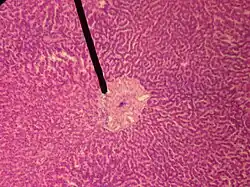

![]() human central vein | |

In microanatomy, the central veins of liver (or central venules)[1] are veins found at the center of hepatic lobules (one vein at each lobule center).

They receive the blood mixed in the liver sinusoids and return it to circulation via the hepatic veins.[2]